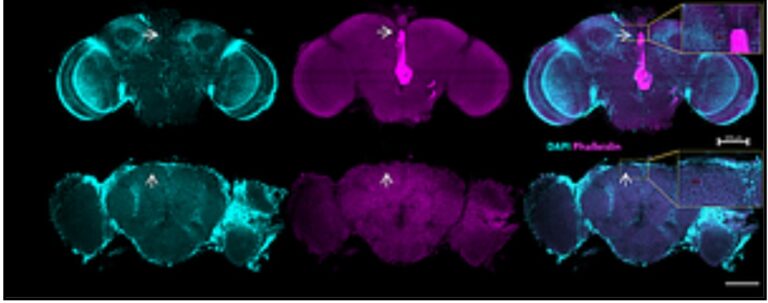

צילום מיקרוסקופי: בשורה העליונה-צילום מוח של זבוב רגיל, ובשורה התחתונה מוח של זבוב עם ניוון עצבי, המראה חורים במוח". קרדיט: שי קלוקסי

אנזים שמונע הפרעות שינה ומצב רוח

החוקרים הראו שמחסור ב-SIRT6 (היורד עם הגיל) מנתב טריפטופן למסלול הקינורנין הנוירוטוקסי על חשבון יצירת סרוטונין ומלטונין; עיכוב האנזים TDO2 בזבובי פירות הפחית נזק מוחי והידרדרות נוירו-מוטורית. הממצאים פורסמו ב-Nature